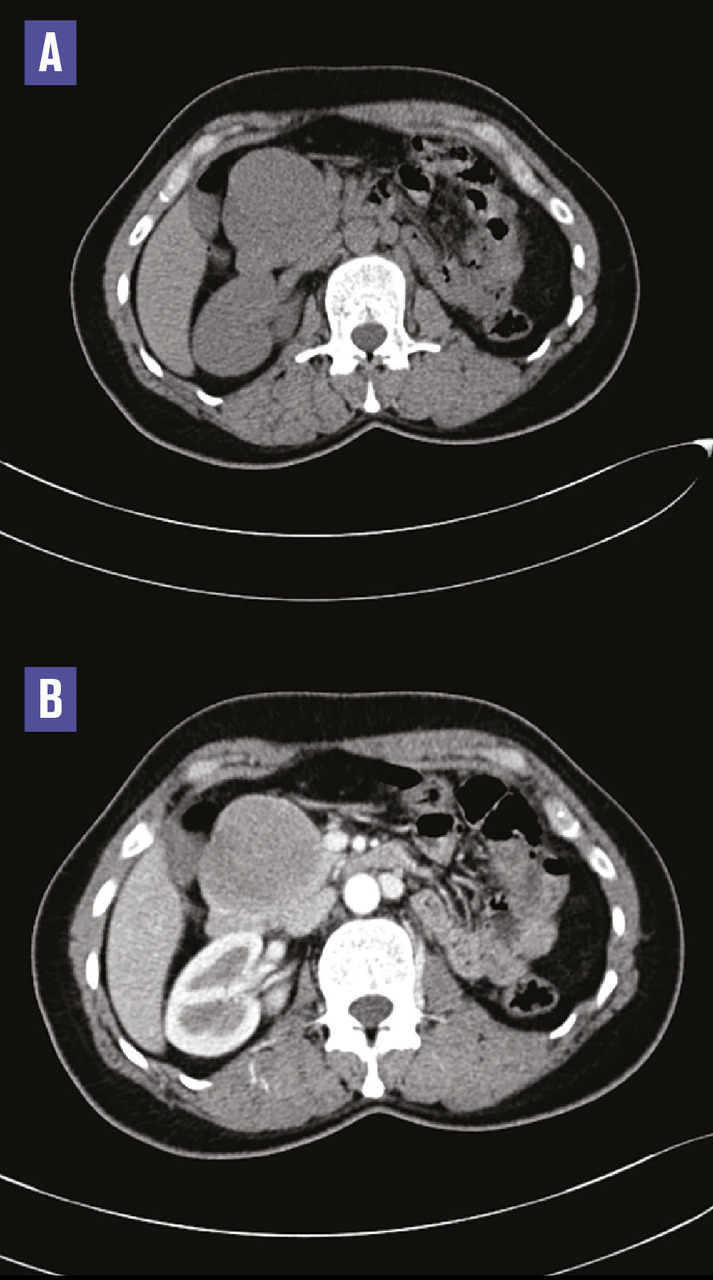

Cette femme de 38 ans était admise aux urgences pour des épigastralgies sans antécédent pathologique notable, avec une fièvre à 38,6 °C ; le bilan biologique mettait en évidence un syndrome inflammatoire sans perturbation du bilan hépatique. La tomodensitométrie abdomino-pelvienne sans et avec contraste réalisée (fig. 1 ) montrait une masse de la tête du pancréas, bien limitée, de 65 x 60 mm, isodense, réhaussée de façon hétérogène, délimitant des zones hypodenses. L’imagerie par résonance magnétique (IRM) pancréatique objectivait une masse de la tête du pancréas en isosignal T1, signal intermédiaire T2, de rehaussement périphérique délimitant une zone centrale liquidienne (fig. 2 ). Une duodéno-pancréatectomie céphalique était réalisée, permettant le diagnostic histologique de tumeur pseudopapillaire et solide du pancréas.

Les tumeurs solides pseudo- papillaires du pancréas sont rares (environ 1 % des tumeurs du pancréas exocrine). Elles surviennent préférentiellement chez les femmes (90 %) jeunes.1 Elles ont un faible potentiel de malignité et peuvent bénéficier d’un traitement chirurgical curatif, mais des récidives sont observées dans 15 % des cas sous la forme de métastases hépatiques ou péritonéales.2 L’IRM est l’examen de choix pour visualiser les composantes kystiques, les remaniements hémorragiques intralésionnels et la présence d’une capsule, sous forme d’un liseré hypo-intense sur les séquences pondérées T2, qui sont caractéristiques de ces tumeurs du pancréas.1 Le traitement est l’exérèse chirurgicale, avec étude anatomopathologique.